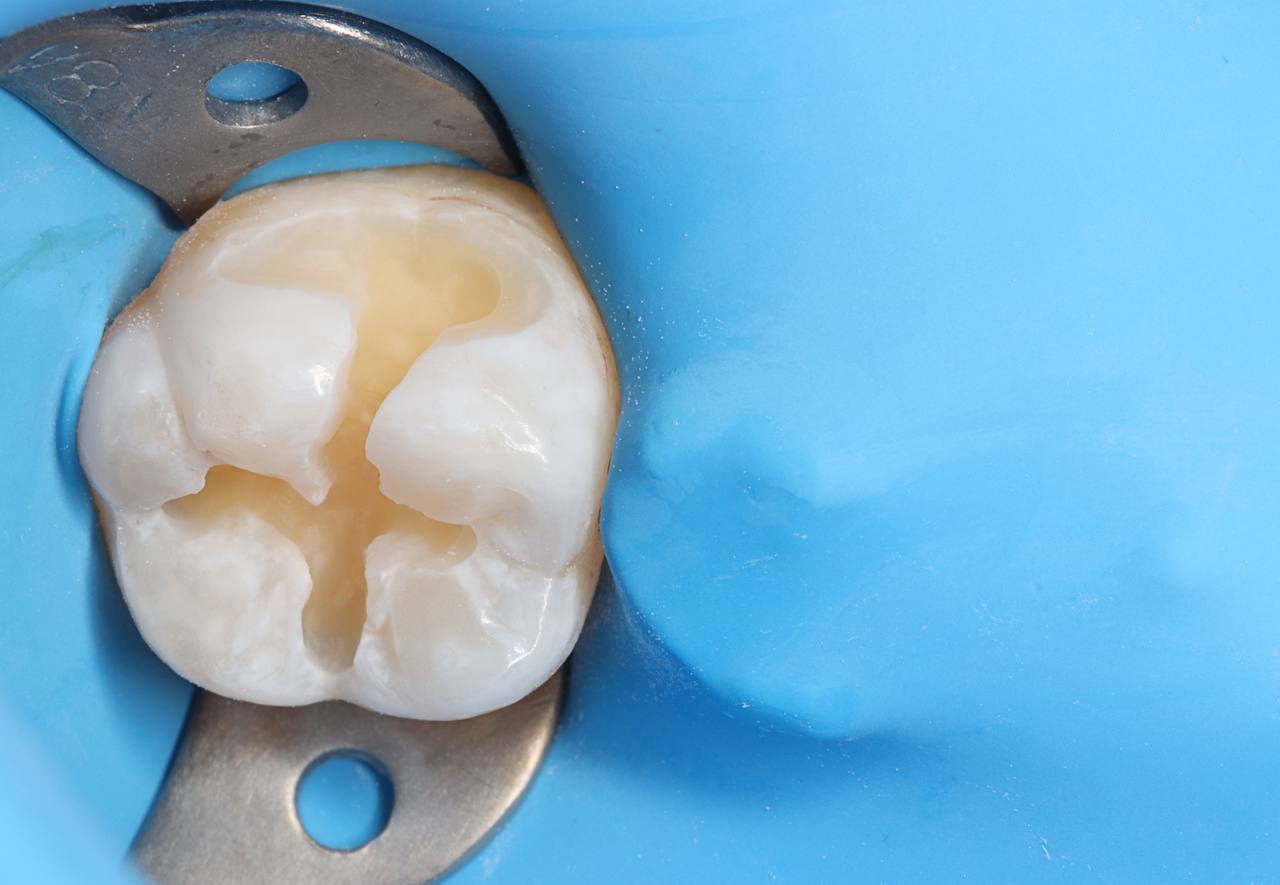

3. Post-operative view of the restoration after contouring. Stain application: BROWN by G-White in the fissure area to mimic pigmented fissures. (Images 3, 4)